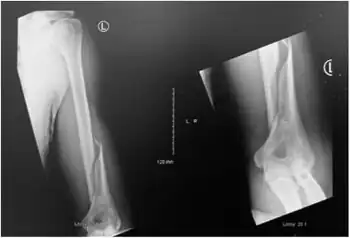

Holstein–Lewis fracture

| Holstein–Lewis fracture at 5 weeks post fracture | |

A Holstein–Lewis fracture is a fracture of the distal third of the humerus resulting in entrapment of the radial nerve.